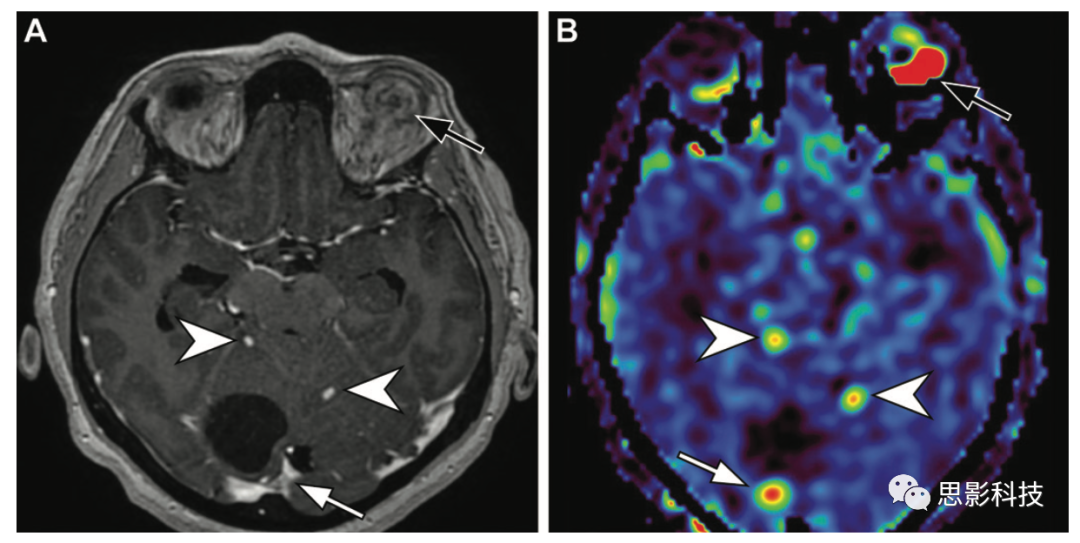

14 48歲男性von Hippel-Lindau綜合征患者的小腦和視網(wǎng)膜血管母細(xì)胞瘤。

(A)軸位高分辨率增強(qiáng)后T1加權(quán)成像顯示右側(cè)小腦邊界清晰的均質(zhì)囊變(低信號(hào)區(qū)域),壁結(jié)節(jié)明顯強(qiáng)化,代表一個(gè)小腦血管母細(xì)胞瘤(白色箭頭),另外兩個(gè)小血管母細(xì)胞瘤(箭頭),以及一個(gè)左眼有強(qiáng)化病變的視網(wǎng)膜血管瘤(黑色箭頭)。

(B)ASL MRI顯示所有四個(gè)血管母細(xì)胞瘤的實(shí)體成分(白色和黑色箭頭)的灌注增加,可與單純囊性病變(低信號(hào)區(qū)域)相區(qū)別。